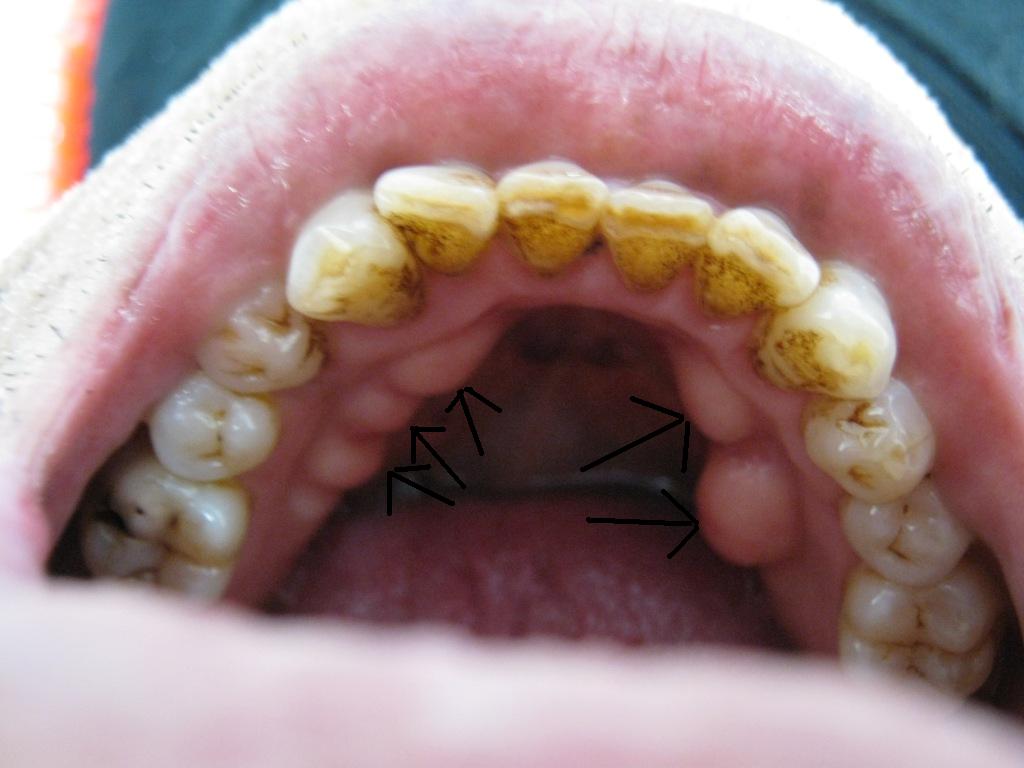

ad10d5ca.JPGそしてこれ、歯茎にコブがある人が多い

基本的に「噛みたい」人の病気である

骨の密度が高くなり、コブさえ出来る程の骨密度

いったい何百キロの力で噛んでいるのか?

コブのある人は歯がなくなった場合も入れ歯ができない

手術してコブをとってから入れ歯を作るという・・・辛い目に合わなくてはならない